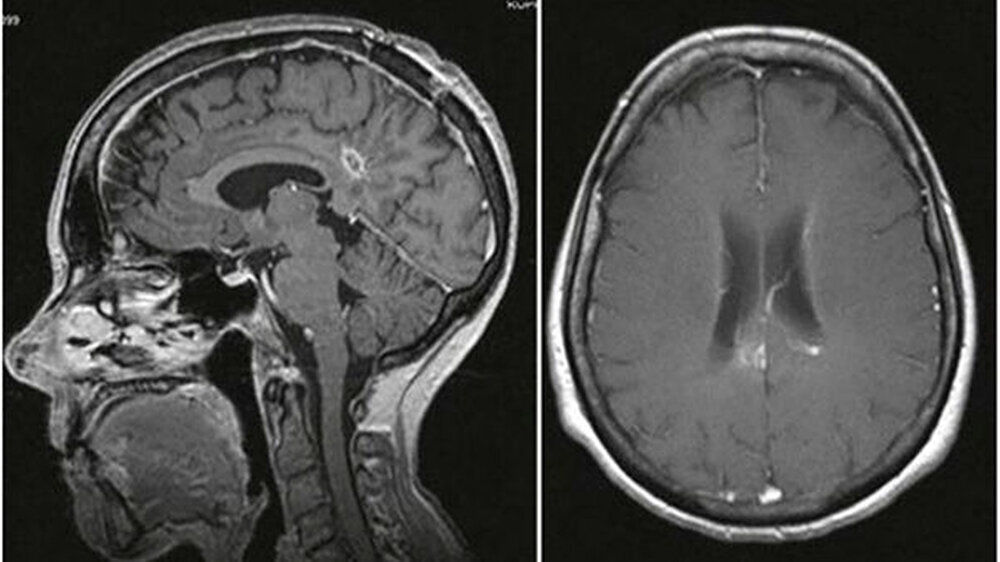

Eine Computertomografie (CT) ergab eine raumfordernde Läsion in der rechten Hemisphäre. Eine anschließende Magnetresonanztomografie (MRT) stellte eine 17 × 15 × 25 Millimeter umfassende Läsion mit einem perifokalen Ödem dar (Abb. 1).

Die Patientin wurde für weitere Maßnahmen an das Departement für Neurochirurgie des Universitätsklinikums Freiburg überwiesen. Auf Grundlage der Bildgebung und einer ehemaligen Brustkrebserkrankung wurde die Verdachtsdiagnose einer Neoplasie gestellt.